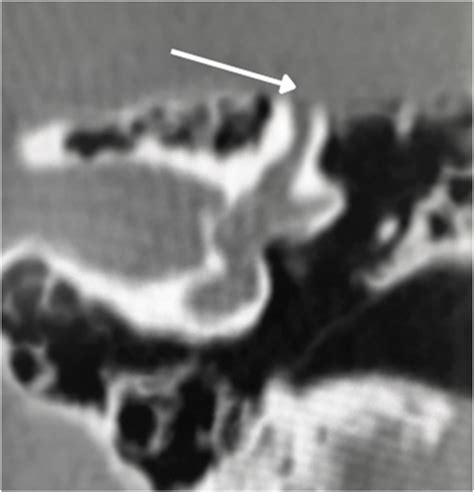

To grasp the complexities of Superior Semicircular Canal Dehiscence, one must first understand the role of the semicircular canals. These structures are vital for balance, filled with fluid that helps the brain track rotational movement. Typically, these canals are encased in solid bone. In patients with SSCD, a small opening or "dehiscence" forms in the superior canal, usually due to developmental defects or prolonged physical stress. This opening acts as a third window, allowing sound and pressure waves to interact directly with the vestibular system, which is not how the ear is designed to function.

Because the inner ear is now hyper-sensitive to pressure changes, even minor stimuli can trigger debilitating symptoms. This phenomenon is known as the third window effect, where sound energy that would normally be funneled to the cochlea for hearing is instead shunted through this abnormal opening, leading to dizziness, vertigo, and unusual auditory sensations.

High-Resolution CT Scan Visualizing the bony opening in the temporal bone.

💡 Note: A standard CT scan is often insufficient; surgeons require high-resolution, thin-cut scans specifically focused on the temporal bone to detect the minute gap in the semicircular canal.